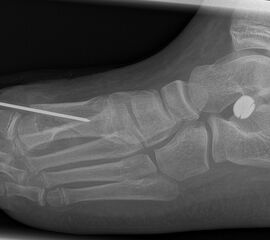

Die Chevron Osteotomie 1 ist ohne Komplikationen am wachsenden Skelett durchführbar. Das Metatarsale I besitzt distal keine Wachstumsfuge, die geschädigt werden könnte. Die „französische Methode nach Marc Elkaim“ eignet sich für Kinder ganz besonders (Abb. 28).

Abb. 28 a-g: Radiologischer Verlauf einer Chevronosteotomie nach dem Verfahren von M. Elkaim mit prä- (a-c drei unterschiedliche Ansichten) und intraoperativen Röntgenbildern in zwei Ansichten (d-e) sowie postoperativ zwei Ansichten (f-g).

Sie wird über eine eigene Tapetechnik fixiert und kann bei einem erhöhten Intermetatarsale-Winkel alternativ zur Scarf-Osteotomie durchgeführt werden. Nachteile der Methode sind eine deutliche Verkürzung durch die Fräse sowie eine starke Plantarisierung des Metatarsale I Köpfchens. Um die Verkürzung zu vermeiden, wird verlängernd in Richtung des Metatarsale II Köpfchens (nicht wie offen in Richtung Metatarsale IV Köpfchen) osteotomiert. Gleiches gilt für die starke Plantarisierung, die durch den Knochenverlust der Fräse entsteht. Die Korrektur eines kindlichen oder jugendlichen Hallux valgus ist mit der Methode ansonsten suffizient durchführbar. Wird verkürzt, muss ausreichend plantarisiert werden, um eine Transfer-Destabilisierung MT II-IV zu vermeiden.

Die MICA-Technik sollte bei geschlossenen Fugen mit einem weitem intermetatarsale Winkel durchgeführt werden. Die dafür typische Verschraubung der Osteotomie kann bei geschlossenen Fugen ohne Probleme erfolgen. Diese Osteotomie kann gut mit einer Akin- und den beschriebenen Kleinzehen-Osteotomien kombiniert werden.